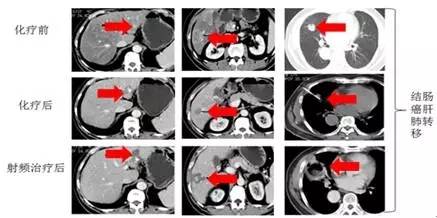

与化疗、放疗联合治疗。化疗、放疗联合射频消融治疗用于转移性肝、肺肿瘤,两者联合应用,可弥补各自的不足以增强疗效。对比任何一种单独治疗模式,延长了患者的生存时间,改善生活质量(见图5)。

图5:患者,男性,58岁,因结肠癌伴远处多发肝、肺多发转移,难以手术及治疗。结合化疗、靶向药物治疗,特别是结合微创射频消融技术成功治愈肝肺转移灶。